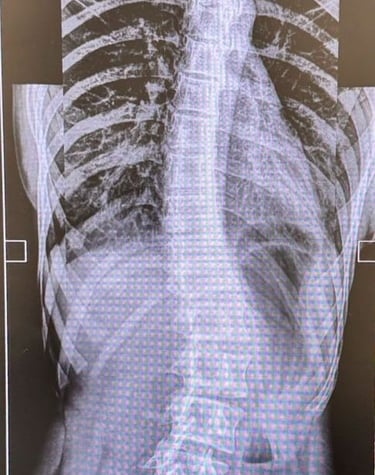

Scoliosis Care

When in doubt about curvatures in your spine - consult doctor to asses the curvatures, plan management.

Gallery

Explore our advanced spine care visuals.